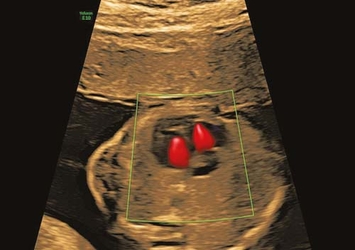

fetale Echokardiographie

fetale Echokardiographie, optimal zwischen 20.–22. Woche

Farbdoppler-Ultraschall

Durchblutung bei Mutter & Kind